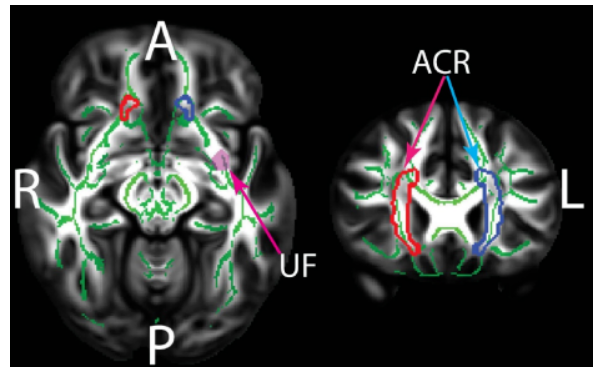

圖1. 在JHU白質(zhì)圖譜中有統(tǒng)計學(xué)意義的白質(zhì)區(qū)域組間差異。ACR: 前放射冠; UF: 鉤束。TBSS骨架和JHU區(qū)域覆蓋在HCP 1065 FA模板上。綠色: 白質(zhì)骨架; 紅色: 右側(cè)前放射冠; 藍色: 左放射冠; 粉色: 左側(cè)鉤束。

研究者選取了38名健康年輕人 (平均年齡23.58歲) 和35名健康老年人 (平均年齡60.91歲),每名被試接受了擴散張量成像 (DTI) 掃描。采用控制性口語單詞聯(lián)想測驗 (Controlled Oral Word Association Test, COWAT;也是一種音位語言流暢性任務(wù), phonemic verbal fluency task) 觀察被試的語言產(chǎn)生能力。采用基于纖維束追蹤空間統(tǒng)計分析 (TBSS) 對12個與語言產(chǎn)生相關(guān)的白質(zhì)區(qū)域 (大腦雙側(cè)的前放射冠ACR、上放射冠SCR、后放射冠PCR、外囊EC、鉤束UF、上縱束SLF,均來自JHU-ICBM-DTI-81白質(zhì)圖譜) 分別進行了分?jǐn)?shù)各向異性 (FA)、平均擴散系數(shù) (MD)、軸向擴散系數(shù) (AD)、徑向擴散系數(shù) (RD) 和局部擴散同質(zhì)性 (LDH) 的基于體素的擴散度量值的組間差異評估。

2. 與老年被試相比, (1) 青年被試在雙側(cè)前放射冠的FA顯著增加; (2) 右側(cè)前放射冠的MD顯著降低,而左側(cè)鉤束的MD顯著增加; (3) 雙側(cè)前放射冠的RD顯著降低; (4) 兩組被試在AD和LDH無顯著差異。